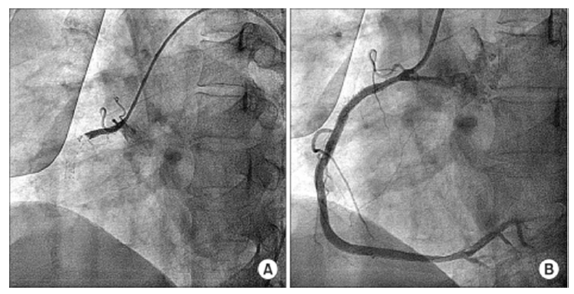

Um paciente procurou o serviço de emergência com quadro de dor torácica típica e foi encaminhado para o setor de hemodinâmica. O procedimento evidenciou lesão coronariana única, representada nas imagens a seguir, antes (A) e após (B) o tratamento da lesão.

Com base nesse caso hipotético, assinale a alternativa que apresenta as alterações encontradas no eletrocardiograma da admissão do paciente.